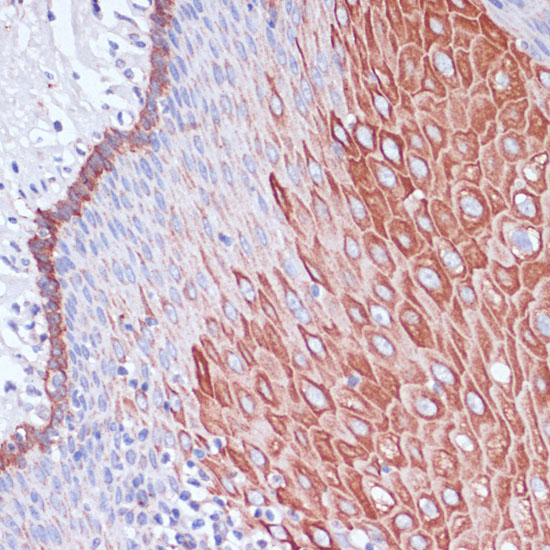

Immunohistochemistry of paraffin-embedded human esophageal using WIPF1 antibody.